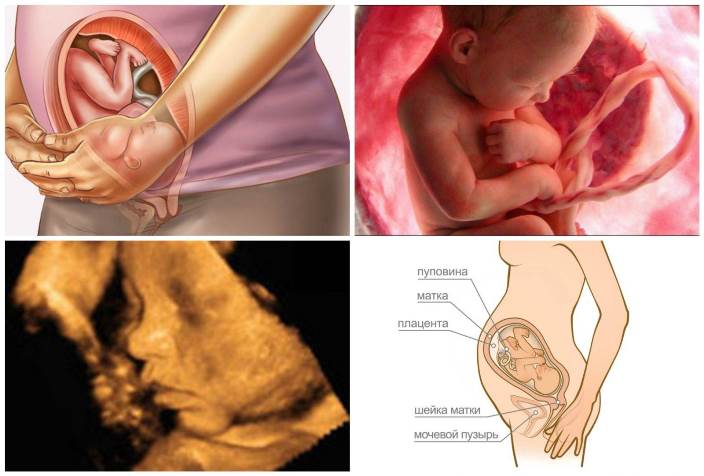

Расположение плода в утробе на 36 неделе. Источник: vagitnist-tyzhden.pp.ua